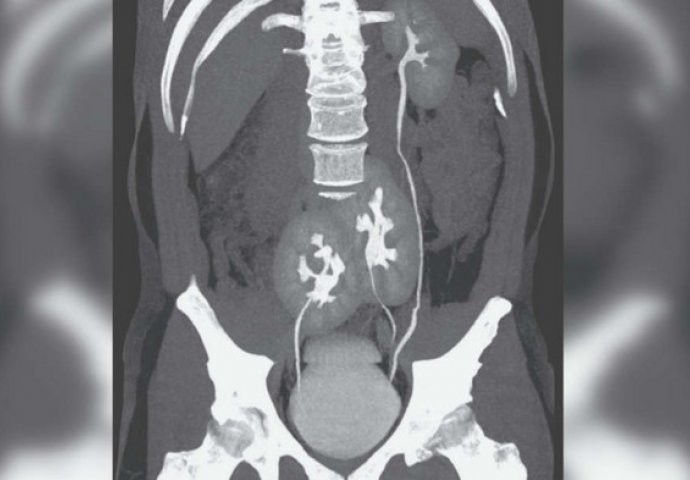

Die Ärzte rieten ihm zu einer Röntgenaufnahme, aber auch sie waren überrascht von dem, was die Aufnahmen zeigten. Die Bilder zeigten, dass er ein gewöhnliches Problem hatte, das täglich behandelt wird, doch außerdem war zu sehen, dass er drei Nieren hat. Auf der linken Seite hatte er eine völlig normale Niere, während sich auf der rechten Seite zwei Nieren befanden, die laut den Aufnahmen miteinander verbunden waren.

Ungewöhnliche Anordnung der Organe

Die Harnleiter waren zu einem einzigen zusammengeführt, direkt am Austritt in die Harnblase. Viele Menschen könnten meinen, dass dieser Mann Glück hat, weil er drei Nieren besitzt, doch dieser Fall ist im Gegenteil sehr ernst. Vielleicht denken Sie, dass eine Niere im Laufe des Lebens ausfallen könnte, wie es bei manchen Menschen oft vorkommt, und der Mann deshalb im Vorteil wäre. Den Ärzten zufolge ist dem jedoch nicht so.